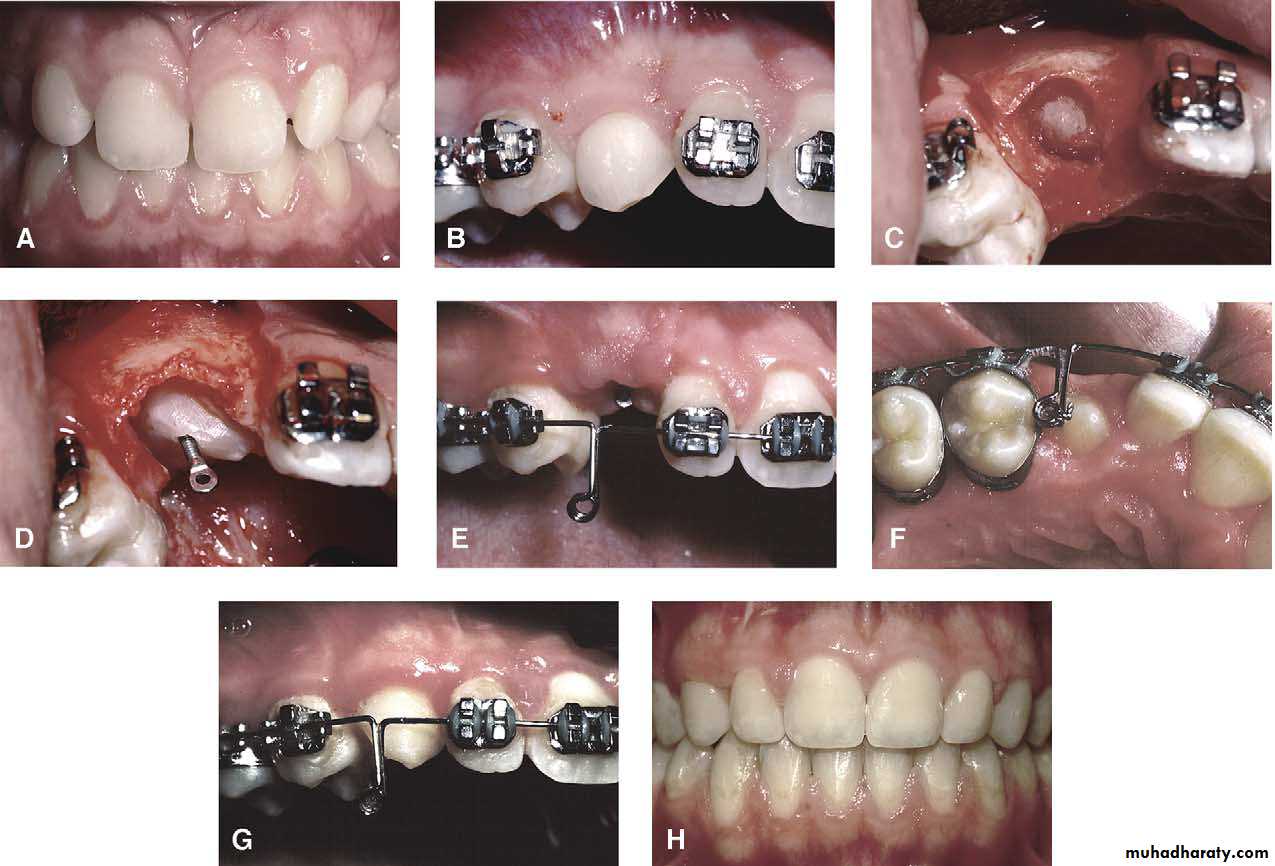

Surgical exposure

An attempt is made to assist the eruption of a malposed and unerupted canine into a functional position . It is considered when :1- there is adequate room in the arch to accommodate the tooth .

2- the potential path of eruption is unobstructed

3- exposure of the crown can be carried out as close as possible to the time at which normal eruption would occur .

Surgical exposure :the path of eruption is not obstructed

Surgical exposure with orthodontic traction: the path of eruption is obstructed

Surgical exposure with orthodontic treatment (palatal approach )

The initial stage of the operation is to reflect the mucoperiosteum and to remove the bone overlying the tooth to expose the greatest coronal diameter, the incisal edge and the cingulum . before repositioning the palatal flap a window is excised in it corresponding to the bony cavity containing the crown .the flap is then sutured as usual and a pack of iodoform gauze should be pressed firmly in to the bony defect so as to cover the exposed crown .

This pack should be held in position with suture and left insitu for 2-3 weeks to prevent granulation tissue and mucosa from overgrowing the denuded crown .after removal of the pack the progress of eruption should be observed at frequent intervals .

Following eruption of the tooth , orthodontic treatment may be required to guide it into a good position in the arch . Some times orthodontic traction is arranged at the time of surgery .